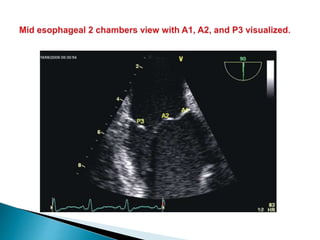

 The posterior leaflet has clefts that divide it into 3 scallops (P1, P2, and P3);

 The anterior leaflet has no such scallops, but is described as having three regions that reflect

those of the posterior leaflet (A1, A2, and A3 respectively).

 In addition to the points of apposition along the leaflets, there are anterior (adjacent to A1/P1)

and posterior (adjacent to A3/P3) commissures.

 The non leaflet apparatus consists of the saddle-shaped mitral annulus, the chordae

tendinae (primary chordae attached to the free edges of the leaflets, secondary and tertiary

chordae attached to body of leaflets), and papillary muscles (anterior: chordae attached to

lateral aspects of leaflets; posterior: chordae attached to medial aspects of leaflets).